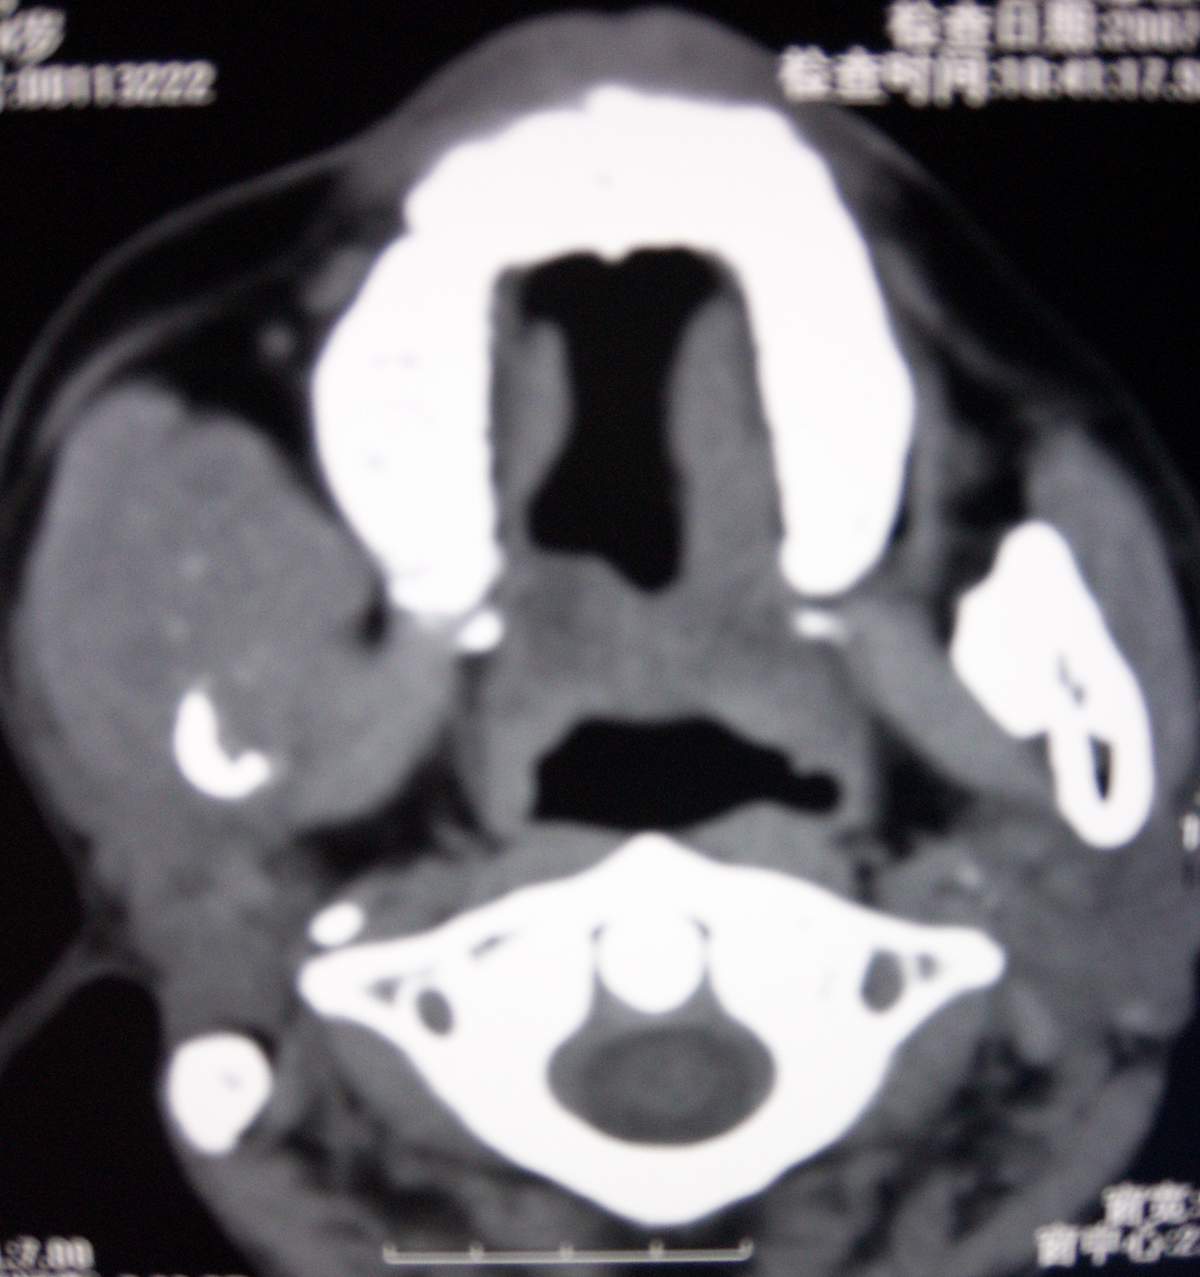

男,54岁,右下颌肿痛1月余。

考虑右下颌骨转移瘤或原发恶性肿瘤,右颈部淋巴结转移.

右侧下颌骨水平部及升支呈溶骨性破坏,无明显膨胀,周围见软组织肿块。

考虑:右侧下颌骨恶性肿瘤或转移瘤。

右下颌骨恶性骨肿瘤伴右颈部淋巴结转移。

右下颌骨溶骨性破坏,代之以团块状软组织影,内有斑片状瘤骨,边缘骨质有少量骨膜反应,考虑:右下颌骨骨肉瘤。期待病理。